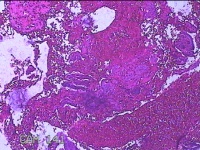

宫颈管内组织

性别

女

年龄

46岁

临床诊断

异常子宫出血

一般病史

阴道流血伴血块6天。

标本名称

大体所见

灰白暗红色不规则碎组织1.5x1.3x0.3cm一堆。

图2